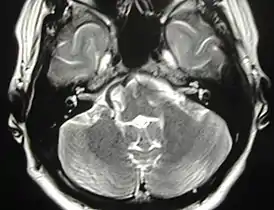

![]() Аксиальная МР-томограмма. Конфликт артериального сосуда с правым лицевым нервом. Клиническая картина: правосторонний гемифациальный спазм. | |